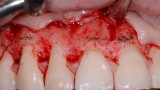

Analiza fotografii z mock-upem potwierdziła konieczność wydłużenia koron klinicznych wszystkich zębów przednich o około 2 mm w kierunku dokoronowym oraz zębów 13-21 w kierunku dowierzchołkowym, w celu zharmonizowania poziomu zenitów dziąsłowych. W związku z tym w okolicy zębów 13-21 wykonano zabieg chirurgicznego wydłużania koron (ryc. 28, 29).